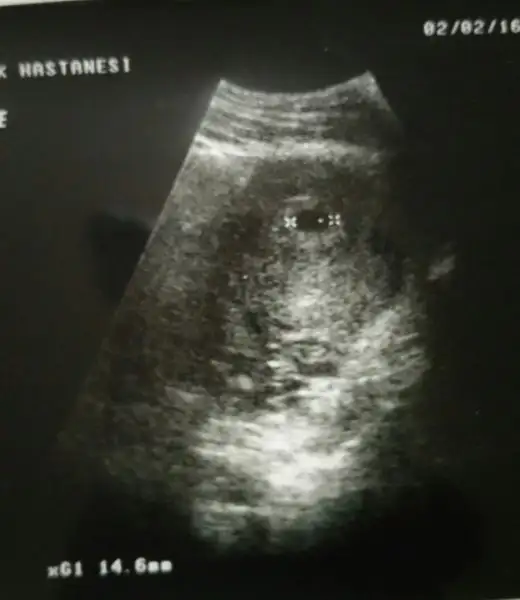

benim ikizlere ne diyorsunuz :) gonlumdekini biliyor rabbimİlk bebişin mi canım. Ben doktoruma direkt sordum. karından ultrasonda plasentasi solda görünüyorsa gerçekte sagda imiş. Usg vajinal ise plasenta diyelim ki solda görünüyor gerçekte de solda imiş. Bende bu teori tutmadı canım. Ama tutan çok fazla hamile var. Benim iki oglumunda plasentasi soldaydı. Plasentanın gerçekte solda olması kız bebek demek.

benim ikizlerde bu yonde seninkiyle ayni konumda icimede kiz doguyor rabbim hislerimi nasip eder insallahBu da benim minis .. bakalım bende öğrenince yazarım..

İnşallah canım, ama benimki istisna normalde solda olunca erkek oluyor :) inşallah seninki de istisnadırbenim ikizlerde bu yonde seninkiyle ayni konumda icimede kiz doguyor rabbim hislerimi nasip eder insallah

burdakide solda benimkide solda ona kiz diyorsun neden ben fark gormedim gonlumden.gecende kiz rabbim gonlumdekini nasip eder insallah arkadasinki iyle benimki ayni konumdacanim arkadasin usg cvp verirmisin